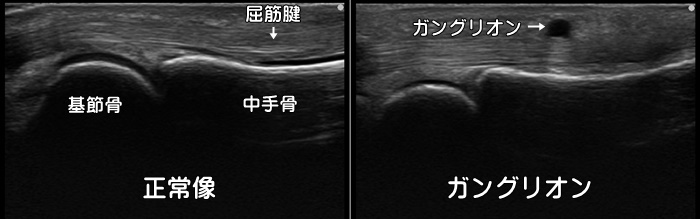

ガングリオン

ガングリオンとはゼリー状の内容物が詰まった腫瘤です。手の甲などにできる事が多いです。

症状が無ければ経過観察で構いませんが神経を圧迫すると痛みや痺れが起こります。

体表からはわからないオカルトガングリオンが手首の痛みの原因になることもあります。

3年間の追跡調査で約8割が自然に消滅します。但し再発もよく起こります。